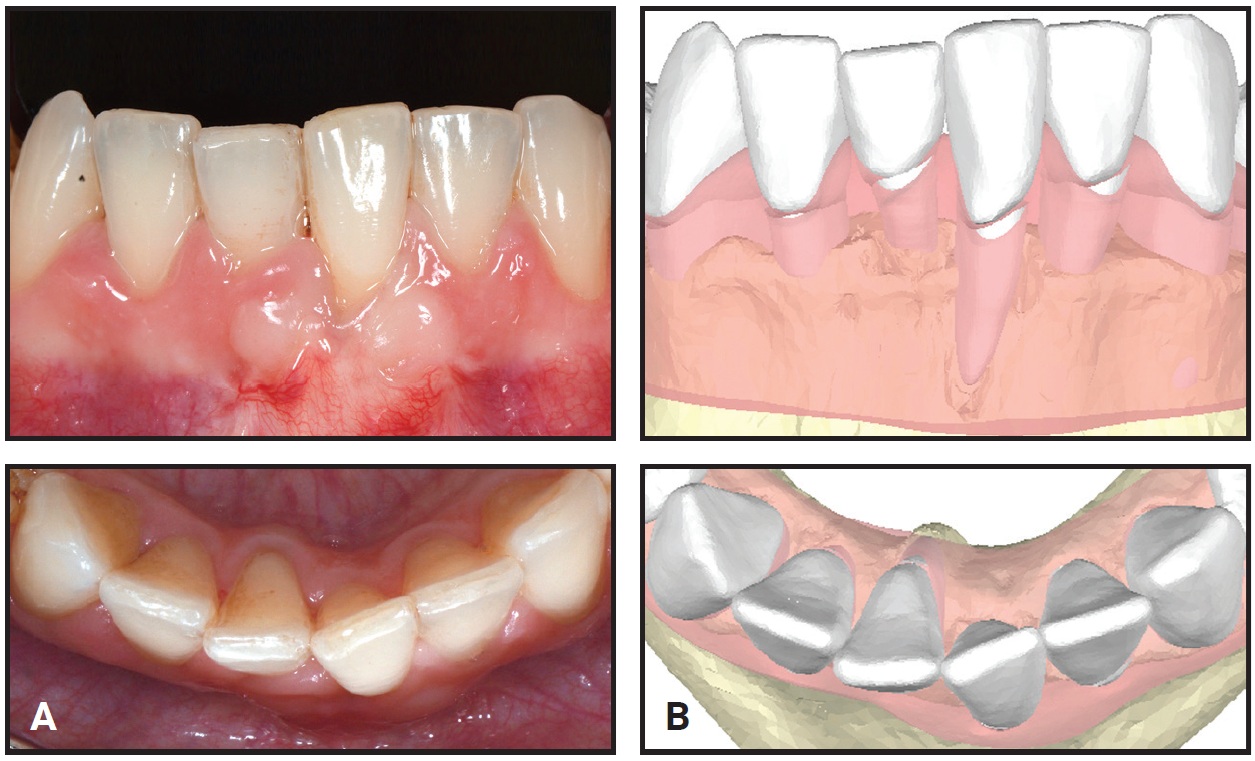

The initial phase of treatment with 23 lower aligners took 12 months; a refinement phase with 10 lower aligners required another three months. At this point, the correct axial inclinations of the lower central incisors had been achieved (Fig. 5), and the roots were properly positioned within the buccal and lingual alveolar bone (Fig. 6).

Fig. 5 A. Lower anterior segment after 15 months of treatment. B. Final root positions of lower central incisors. C. Right incisor properly positioned in lingual cortical bone. D. Left incisor properly positioned in buccal cortical bone.

The changes in torque were 10° for the lower left central incisor and 7° for the lower right central incisor (Fig. 7). The predicted changes were 12° and 10°, respectively, confirming that the virtual 3D model simulation of the final root positions was accurate.